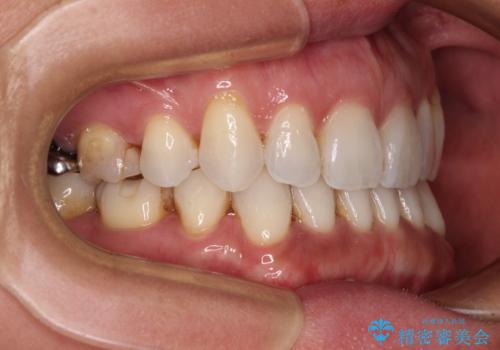

抜歯矯正の後戻りをインビザライン・ライトで解消

- 下顎前歯を中心に、以前行った矯正治療の後戻りが気になるとのことで来院された患者様です。

後戻りは軽度であったため、インビザライン・ライトにて治療を行うこととしました。

矯正治療後は、再度後戻りすることを極力回避するために、下顎前歯の舌側を細いワイヤーを用いて保定することとしました。